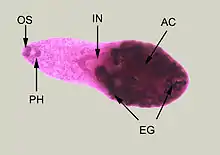

Adult specimen of Heterophyes heterophyes stained with carmine

Heterophyes is a genus of trematodes, or fluke worms, in the family Heterophyidae.[2]